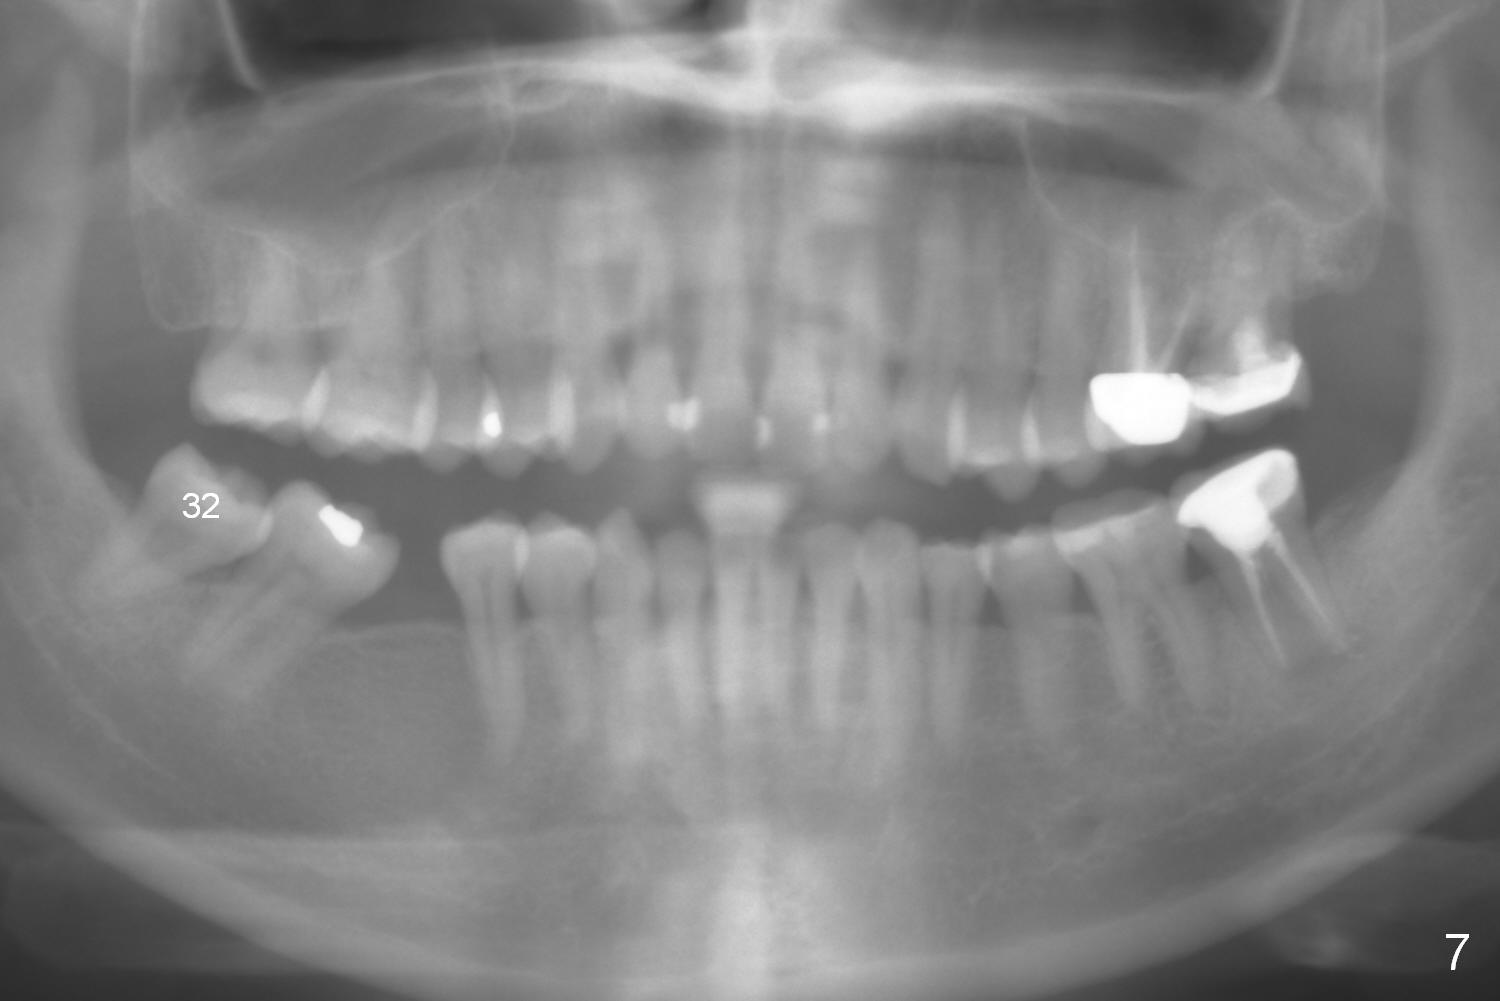

A 38-year-old woman agrees with implant placement at #30 and orthodontic preparation, but she does not like to have the tooth #32 extracted (Fig.7).

Show the patient that the tooth #31 is severely mesially tilted with reduction in the mesiodistal width for implant placement (Fig.5,7). The tooth #32 is severely malpositioned (linguoversion, Fig.6). It is extremely difficult to gain space for the implant without #32 extraction.